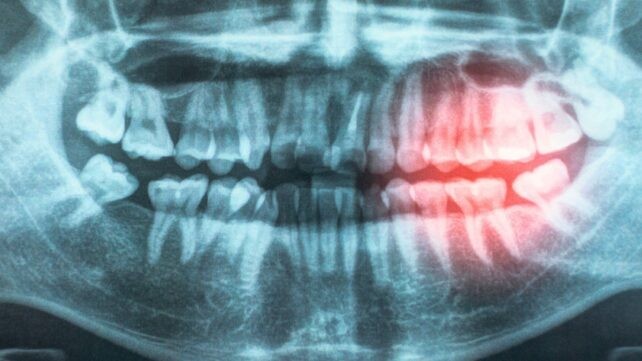

Преглед од Комитетот за превенција на срцеви болести при Американската асоцијација за срце уште повеќе ја зајакнува поврзаноста помеѓу здравјето на непцата и заштитата од срцеви болести. Тие го прегледаа знаењето добиено од една деценија научна литература, која опфаќа генетски истражувања, клинички испитувања и лабораториски тестирања, а новиот извештај претставува ажурирана и засилена потврда дека проблемите со срцето предизвикани од артерии запушени со наслаги (атеросклеротична срцево-садова болест – ASCVD) се тесно поврзани со пародонталните заболувања.

Во истражувањето, научниците ги разгледале можните причини за оваа поврзаност, вклучително и можноста бактериите да влегуваат во телото преку изложените и оштетени непца, предизвикувајќи хронично воспаление. „Вашата уста и вашето срце се поврзани“, изјавува педијатрискиот кардиолог Ендру Тран. „Болеста на непцата и лошата орална хигиена може да дозволат бактериите да навлезат во крвотокот, предизвикувајќи воспаление што може да ги оштети крвните садови и да ја зголеми опасноста од срцеви заболувања.“

Еден од големите предизвици за испитување на оваа врска е тоа што многу ризик-фактори – од пушење, преку стареење, до дебелина – го зголемуваат ризикот и за болести на непцата и за ASCVD. Но, нови докази упорно укажуваат дека постои независна врска меѓу двете состојби. ASCVD останува најчестата причина за смртност во светот, и ако подобрувањето на оралната хигиена може да биде еден од начините за нејзина превенција, тоа вреди да се испита.

Некои од анализираните студии опфаќаат информации за испитаници уште од детството и укажуваат дека раната грижа за забите може да ја намали опасноста од срцеви проблеми во подоцнежна возраст. „Постојат силни докази дека лекувањето на пародонталните болести ги подобрува меѓурезултатите како што се крвниот притисок, нивото на липопротеини со висока густина (HDL) и маркерите за воспаление“, пишуваат истражувачите во објавениот труд. „Ова е важно откритие бидејќи овие параметри се познати како фактори што ја зголемуваат идната срцева опасност и претставуваат можна врска меѓу пародонталните болести и ASCVD.“